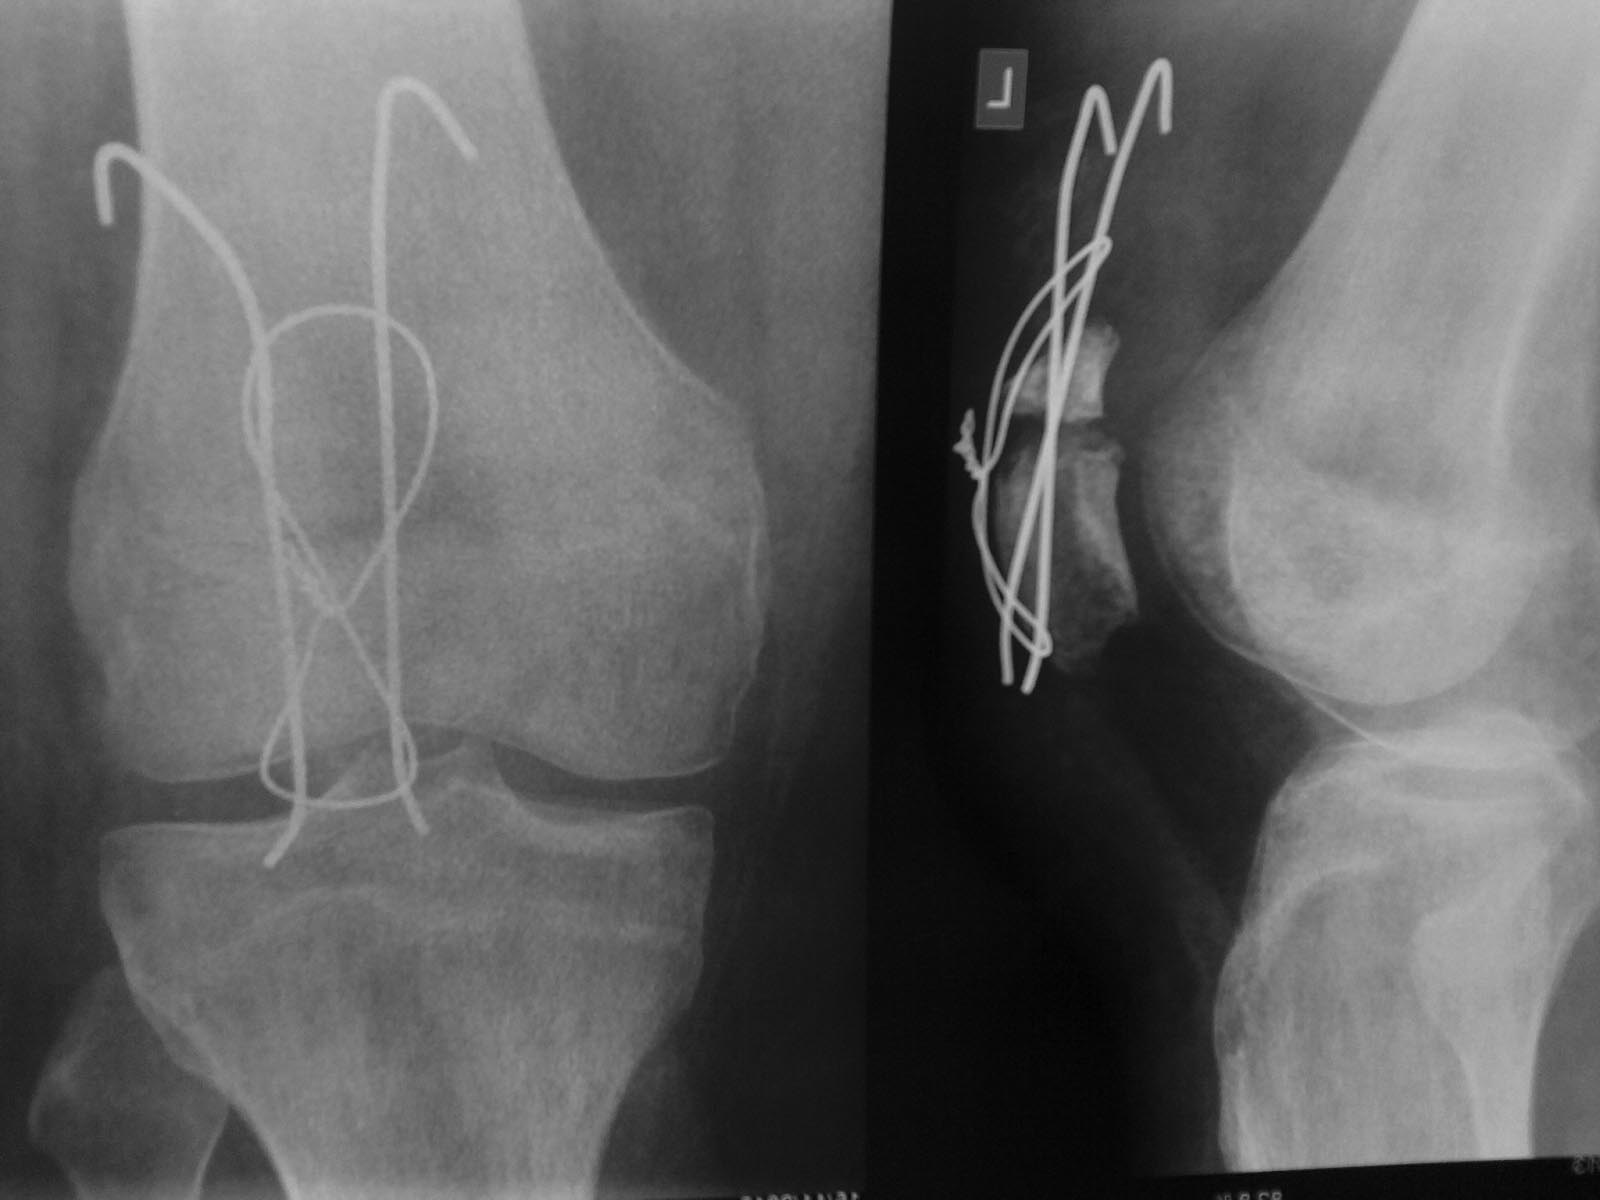

[Ortho] Рефрактура надколенника

повторный осмотр, как и говорил, через 6 недель после операции,

выполнено 3 сеанса ударно-волновой терапии, ходил в ортезе на костылях,

снимая его только для сознательного сгибания в коленном суставе по

150-180 раз на день)

сгибание до 90 градусов (с небольшим дискомфортом в области сухожилия

квадрицепса)

пальпаторно при сильном надавливании на надколенник с небольшим

сгибанием болевых ощущений нет (небольшой дискомфорт) - не знаю, как

иначе проверить нестабильность сегмента

выполнен рентген-контроль, по которому можно ориентироваться на

дальнейшую тактику - действительно реМОС (правда уже технически не знаю

как и чем) или продолжение предыдущего режима

Поделитесь мнениями и опытом